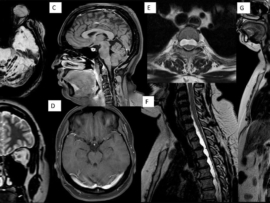

60-year-old adult, chronic smoker with history of angioplasty, presented with recent onset hemoptysis, weight loss and generalized fatigue with mild fever.